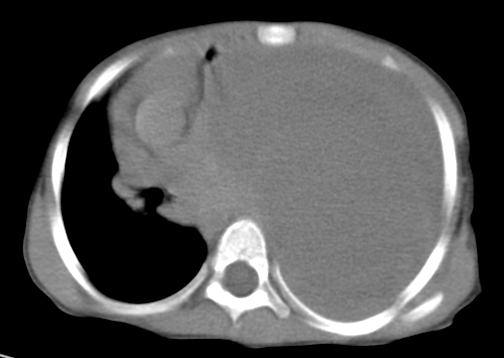

患儿 女 4岁,发热 咳嗽 胸透 考虑:左侧脓胸

左侧胸廓内见大量密实阴影,肺尖部尚有少量肺组织影,纵膈明显受压移位,肋骨未见明显受侵征象,虽然病人年龄较小,但如此大量的“积液”,还是要警惕,不同意一般感染,可结合穿刺脱落细胞学检查。

1)考虑左肺炎症感染。2)左侧大量胸腔积液。

1)考虑左肺炎症感染。2)未经穿刺只能定左侧大量胸腔积液。

左侧张力性大量胸腔积液压迫性肺不张、感染;建议治疗后复查。